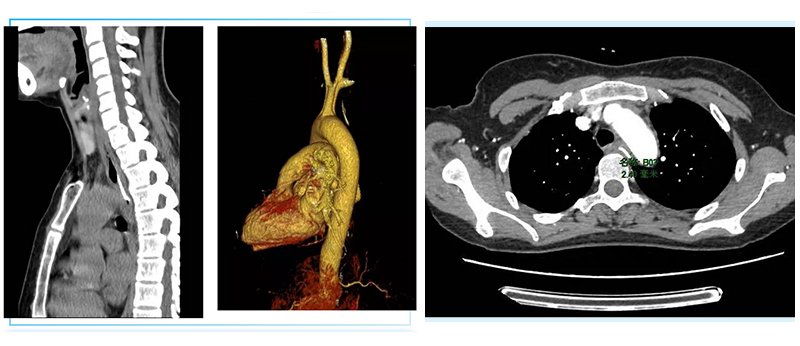

The patient, 48-year-old female, mistakenly swallowed a fish bone when having dinner on March 19th, and she went to the local hospital for chest CT examination. The image showed that there was a foreign body on the middle segment of esophagus (T3-4 vertebral body level). It showed a flap-like high-density shadow with a length and diameter of about 2.8cm. Chest CTA showed the foreign body was about 2.4mm from the aortic arch.

Chest CTA showed the foreign body is about 2.4mm from the aortic arch.